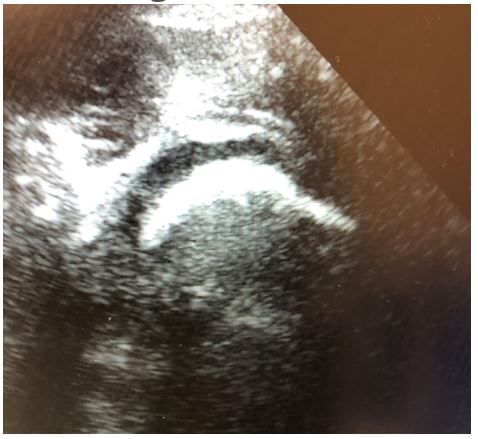

Imaging: see ultrasound image below